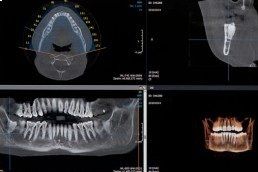

Ulteriore metodica di ultima generazione, la Cone Beam 3D, disponibile presso il Centro di Sciacca e di Ribera, si avvale di raggi X per acquisire una porzione del massiccio facciale, in particolare le arcate dentarie. La Cone Beam 3D viene utilizzata prevalentemente nella valutazione pre-operatoria in implantologia dentale.

Il macchinario di recente installazione che utilizziamo al Centro Radiologia Tagliavia, la Cone Beam Orthophos SL, permette l’acquisizione del volume desiderato in pochi secondi e attraverso le tecniche di post-processing e le ricostruzioni 3D, consente una migliore pianificazione pre-operatoria (misurazioni, densità) e una immediata visualizzazione delle arcate dentarie.

La Cone Beam 3D consente una riduzione nella dose di radiazioni somministrate rispetto a una TAC dentale, con buona qualità diagnostica limitatamente allo studio delle arcate dentarie: morfologia, altezza e spessore dell’osso sede di impianto, inclusioni dentarie (rapporti con il canale mandibolare), studio dell'articolazione temporo-mandibolare.